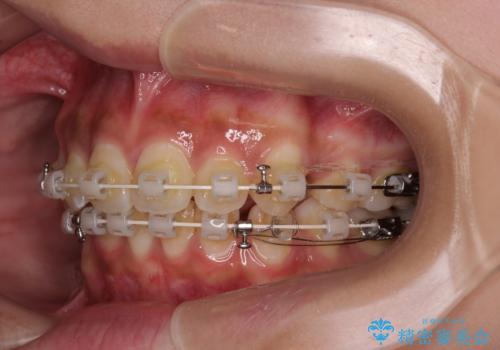

- 矯正装置

- 審美装置

- 下唇に上顎前歯の跡がつくくらいに突出した前歯とデコボコを気にして来院された患者様です。

口元の突出感改善のため、上下左右の第一小臼歯4本を抜歯し、ワイヤー装置にて矯正治療を行うこととしました。

それほど口元の突出感が強いわけではありませんでしたが、下唇に前歯引っかかる感触が気になっていたため、抜歯矯正を行うこととしました。

上下前歯の被蓋が理想通りに改善され、患者様には大変満足していただけました。